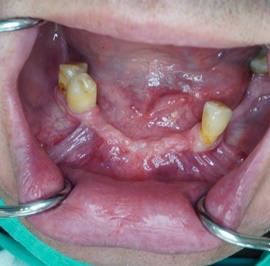

Pacjentka głosiła sie do naszego gabinetu do leczenia z osadzonym mikroimplantem w pozycji lewej dolnej dwójki. Siostrzany implant w pozycji prawej dolnej dwójki wypadł wcześniej, około 1,5 roku od implantacji. Odtworzono przedsionek i dziąsło rogowaciejące, osadzono dwa implanty, jednoczasowo z regeneracją kości. Dopiero na etapie ostatecznej rekonstrukcji protetycznej usunięto zachowany mikroimplant. To się nazywa motywacja do leczenia! Pacjentka przygotowywała sie na ślub prawnuczki :)